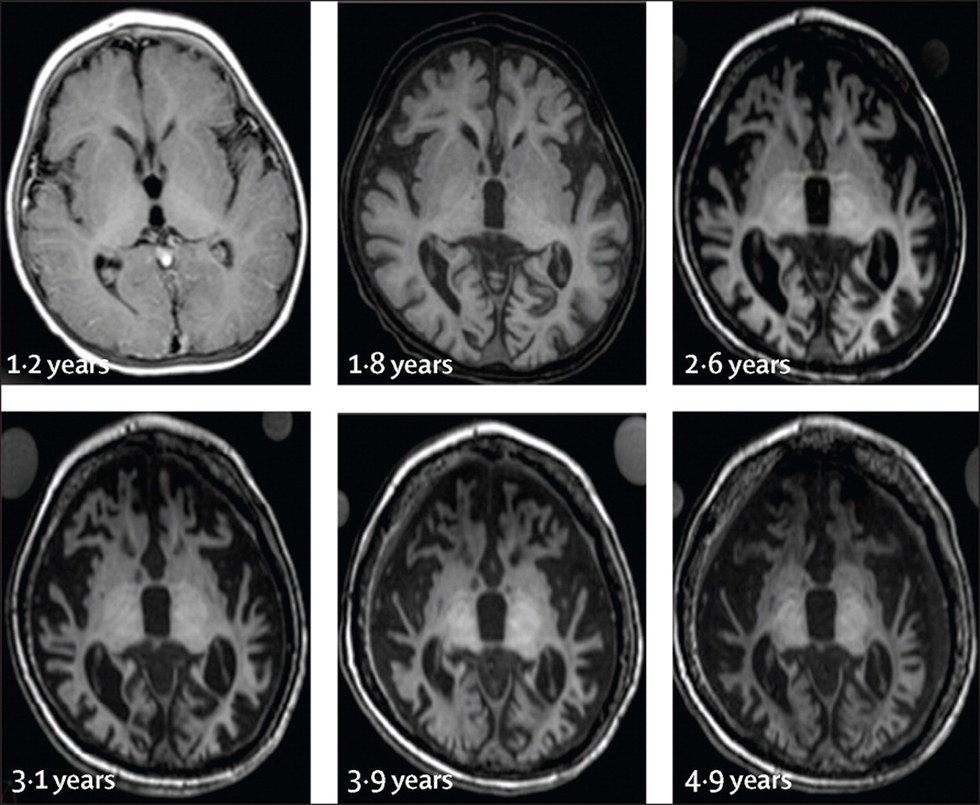

You can very clearly see the atrophy of the brain of an NCL patient here. The white is brain matter. By 4-9 years, there is almost brain matter left.

Batten Disease is a neurodegenerative disease, which means it is a disease that affects the brain, and only gets worse. It is called a lysosomal storage disorder because the lysosomes in cells, the part of a cell responsible for waste disposal, are incapable of breaking down a particular fatty acid waste product. The body cells (most notably the brain cells) are incapable of ridding themselves of toxins because the cells lack an enzyme to break down the wastes. These waste products build up in the cells until the cells die. The simple explanation is that Mabel’s body destroyed its own brain.